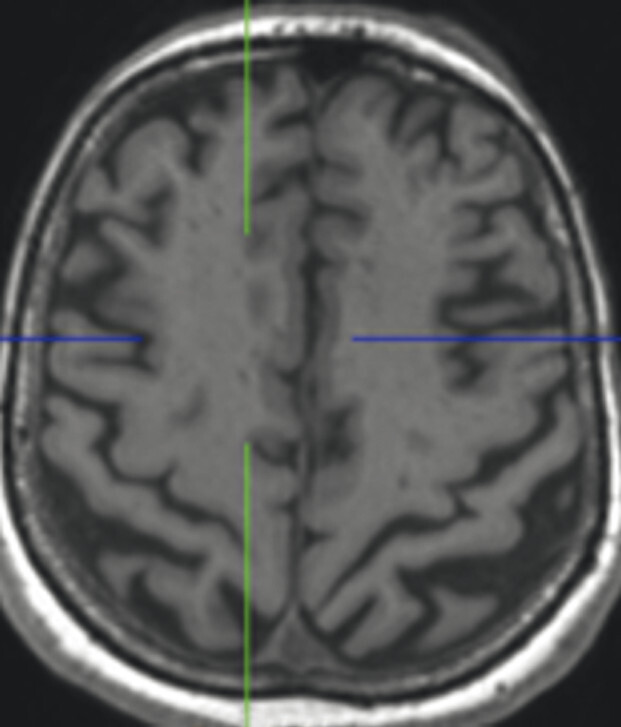

Abb. 69.10 Parkinson-Syndrome: Differenzialdiagnose progressive supranukleäre Parese mit Parkinson-Syndrom.

74-jähriger Patient mit linksbetontem Parkinson-Syndrom und aktuell deutlicher demenzieller Entwicklung mit exekutiver Störung und Zeitgitterstörung. In der T1w 3-D-MRT zeigt sich ein unauffälliges Mesenzephalon (a) mit einer normalen Midbrain/Pons-Ratio von 0,61 (kurzer Durchmesser des Mesenzephalons: 9,9 mm; kurzer Durchmesser des Pons: 16,1 mm, beide durch eine rote Linie dargestellt; b). Die automatisierte Ganzhirnvolumetrie (c) lässt außerdem ein anomales Hirnvolumen frontal bis parietal beidseits erkennen. In der 2 mm dünnen transversalen SWI-Schicht findet sich kein Schwalbenschwanzzeichen (d).

a T1w 3-D-MRT-Sequenz.

b T1w 3-D-MRT-Sequenz mit eingezeichneten Durchmessern.

c Ganzhirnvolumetrie.

d Transversale SWI.